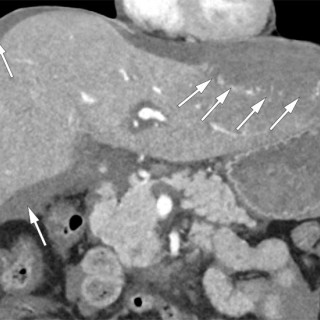

CT-bildene er fra en undersøkelse med opptak uten intravenøs kontrast. Bildet til venstre viser høy attenuasjon i myokard i venstre ventrikkel, og i mindre grad i høyre ventrikkel. Attenuasjonen er tilnærmet lik skjelett i bildet, og tettheten kan passe med forkalkninger. Opptaket er gjort på en spektral-CT, som har økt mulighet for å differensiere mellom ulike vevstyper. Maskinen utnytter de ulike energinivåene i røntgenstrålen, og den kan skille mellom grunnstoffer som jod og kalk utfra absorpsjonsnivået, da begge gir høy attenuasjon. Kalksuppresjon, vist på bildet til høyre (B), bekrefter...